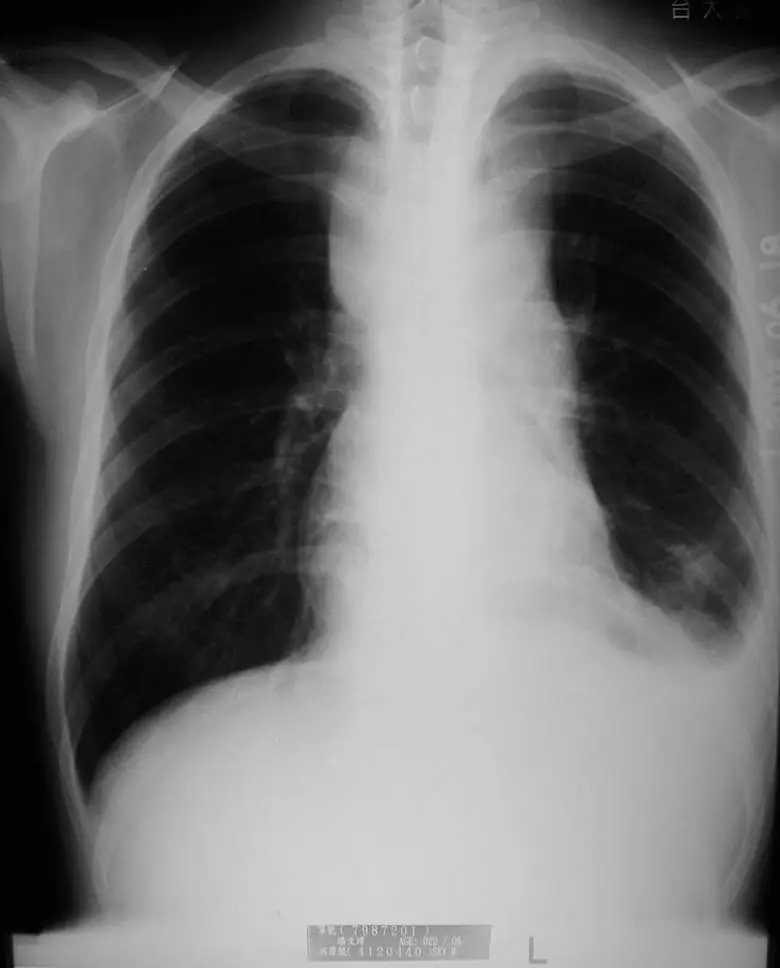

一位 18 歲男性因頸部淋巴結腫大應診,抽血檢查發現血紅素為 12.5 gm/dL ,白血球 3550/ µL,其中 blast 2% ,血小板 135000/ µL。胸部 X光如圖所示。此病人最可能的診斷為何?

胸部正面 X 光(CXR)顯示右側前縱膈出現顯著的縱膈腔增寬(mediastinal widening)及前縱膈腫塊(anterior mediastinal mass),腫塊邊緣清晰,向右側肺野突出,壓迫右側正常肺實質。左側肺野相對清晰,心臟輪廓大致正常。無明顯胸腔積液或肺浸潤跡象。

前縱膈腫塊(anterior mediastinal mass)的鑑別診斷記憶口訣為「4 T's」:

- Thymoma(胸腺瘤)

- Teratoma/Germ cell tumor(畸胎瘤/生殖細胞腫瘤)

- Terrible lymphoma(淋巴瘤)

- Thyroid(甲狀腺腫延伸)

在 18 歲青少年男性合併頸部淋巴腺腫大及周邊血液異常的情境下,淋巴瘤(尤其是 T-LBL)是最優先考慮的診斷。